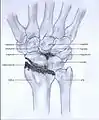

Wrist osteoarthritis is gradual loss of articular cartilage and hypertrophic bone changes (osteophytes). While in many joints this is part of normal aging (senescence), in the wrist osteoarthritis usually occurs over years to decades after scapholunate interosseous ligament rupture or an unhealed fracture of the scaphoid. Characteristic symptoms including pain, deformity and stiffness. Pain intensity and incapability (limited function) are notably variable and do not correspond with arthritis severity on radiographs.

Osteoarthritis of the wrist can be idiopathic, but it is mostly seen as a post-traumatic condition.[1][2] There are different types of post-traumatic osteoarthritis. Scapholunate advanced collapse (SLAC) is the most common form, followed by scaphoid non-union advanced collapse (SNAC).[3] Other post-traumatic causes such as intra-articular fractures of the distal radius or ulna can also lead to wrist osteoarthritis, but are less common.